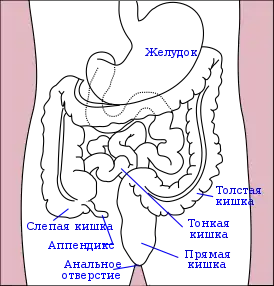

Расположение аппендикса в брюшной полости | |

Аппендици́т (лат. appendicitis) — воспаление червеобразного отростка слепой кишки (аппендикса) разной степени выраженности. Одно из наиболее частых заболеваний брюшной полости, требующих хирургического лечения.